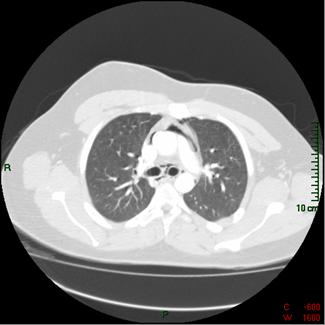

An 18-year-old man presents to the emergency department stating he felt like he “was going to die.” While on break at work, he experienced sudden onset sharp, midsternal chest pain. He had no dyspnea or radiation of the pain. He had not suffered any recent chest trauma but did strike his head on a piece of equipment at work without sequelae. Three days prior to presentation he had cough productive of yellow sputum without fevers or chills. At the time of evaluation, the pain had been present for several hours and was only relieved by narcotic medications.

His past medical history was significant for bipolar disorder, which was controlled without medications. He worked as a stock clerk at a department store. He was a current smoker, 1 pack per day for 2 years, and he gave a history of prior cocaine use, but denied any recent illicit drug usage.